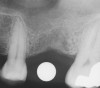

Sinus Floor Elevation in a Socket

The sinus floor elevation technique can be used when a tooth is extracted and there is not enough bone height to support an immediate implant (Figure 8, Figure 9 and Figure 10, Figure 11).32

Figure 8  At site No. 13 the second bicuspid had a hopeless prognosis; it was to be extracted and replaced with an implant after a transcrestal sinus floor elevation.

Figure 8

Figure 9: After the extraction, a 2.1-mm twist drill was used to drill within 1 mm of the subantral floor. A guide pin was placed and a radiograph was taken to ascertain if the drill stopped within 1 mm of the subantral floor.

Figure 9

Figure 10  The osteotomy was completed with the 2.1-, 2.8-, and 3.5-mm twist drills without penetrating into the sinus. After infracturing the subantral wall with a 3.5-mm osteotome, bone was added and the presence of a dome was confirmed with a radiograph.

Figure 10